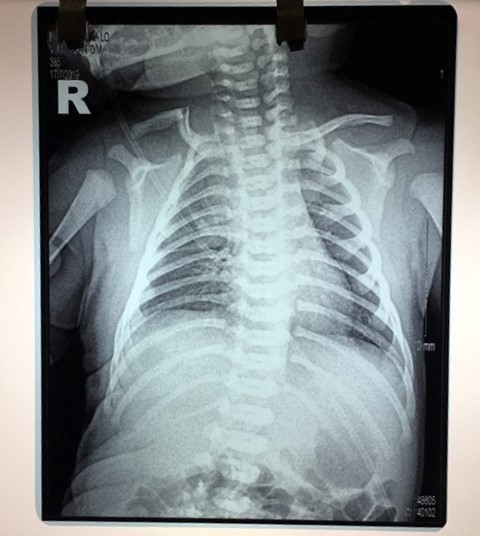

Hình ảnh X Quang cho thấy cháu bé bị gãy xương đòn |

Tại Trung tâm y tế huyện Nghĩa Lộ các bác sĩ sau khi thăm khám, chụp phim và có kết: “Cháu bị gãy xương đòn” nên gia đình chuyển xuống Bệnh viện nhi Trung Ương để điều trị. Tại Bệnh viện nhi Trung ương chẩn đoán: "Gãy xương đòn do chấn thương khi sinh". Sau khi được các bác sĩ Bệnh viện Nhi trung ương điều trị và nẹp chun tình hình của cháu đã ổn định và ít quấy khóc như trước.

Kết quả xét nghiệm cho thấy cháu bé bị "Gãy xương đòn do chấn thương kho sinh". |